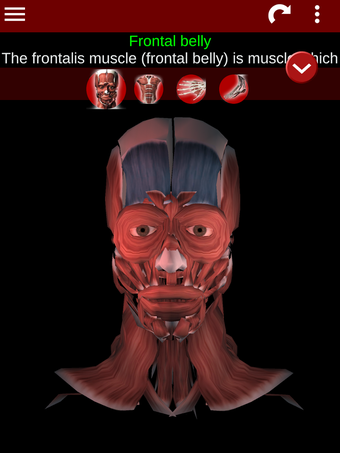

Esta herramienta educativa proporciona una descripción de cada músculo del cuerpo humano, así como un modelo tridimensional del sistema muscular. Con sólo tocar con el dedo, la aplicación revelará la información pertinente.

Los usuarios pueden hacer zoom sobre el músculo, así como elegir si ocultar o mostrar los datos. La orientación puede ser horizontal o vertical, según convenga más.